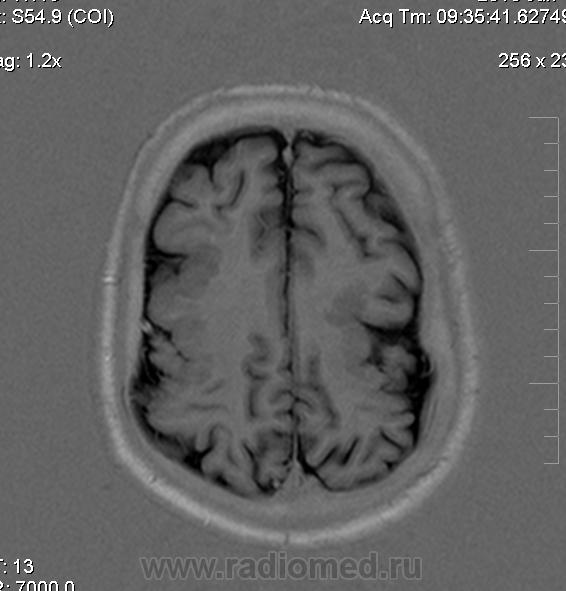

Мужчина 32 лет. Из анамнеза: перинатальное повреждение ЦНС, ДЦП, дизартрия, правосторонний верхний монопарез. С 16 лет приступы эпилепсии.

Аплазия прозрачной перегородки. Шизэнцефалия с открытыми краями в лобно-теменной области слева. Шизэнцефалия с закрытыми краями в лобной области справа? Утолщение коры по контуру расщелин и в области глазничной извилины правой лобной доли. Микрогирия? Гиперостоз костей свода черепа. Уважаемые коллеги, возможно я ошибаюсь, или есть еще аномалия?

Спасибо. Как тогда лучше сформулировать заключение? МР-картина кортикальной дисплазии : двусторнняя шизэнцефалия с утолщением коры по контуру расщелин, микрогирия в лобной области справа, очаг гетеротопии серого вещества в области  глазничной извилины правой лобной доли. Признаки септооптической дисплазии (гипоплазия зрительных нервов, аплазия прозрачной перегородки). Лиссэнцефалии не вижу. Есть сомнения по поводу шизэнцефалии справа (может быть я запуталась в микрогирии и мерещится шизэнцефалия?) Нет ли какой либо анамалии развития черепа?

На мой взгляд, полимикрогирия двусторонняя (конвекситальные отделы дорзальных отделов лобных долей и частично теменных, а также в базальном отделе полюса правой лобной доли) + закрытая шизенцефалия левой лобно-теменной области. Аплазия прозрачной перегородки (как признаки лобарной голопрозенцефалии).